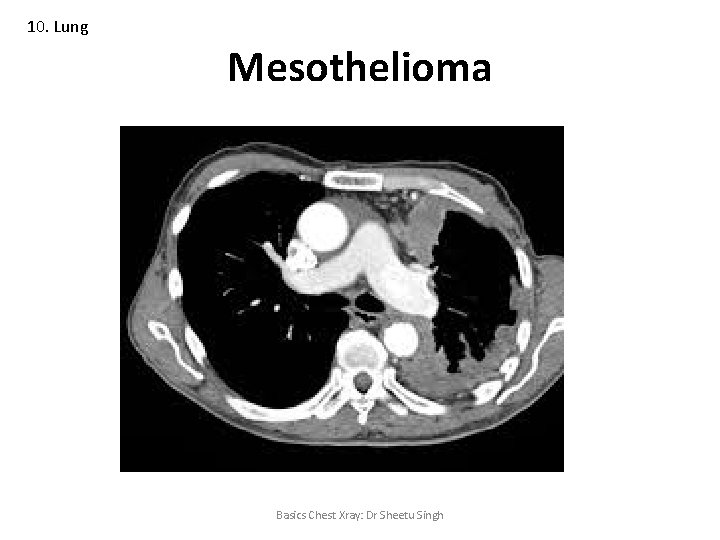

10. Lung Mesothelioma Basics Chest Xray: Dr Sheetu Singh

10. Lung Asbestosis • Pleural plaques (primarily the diaphragmatic pleura) • Pulmonary fibrosis • Mesothelioma • Lung cancer Basics Chest Xray: Dr Sheetu Singh